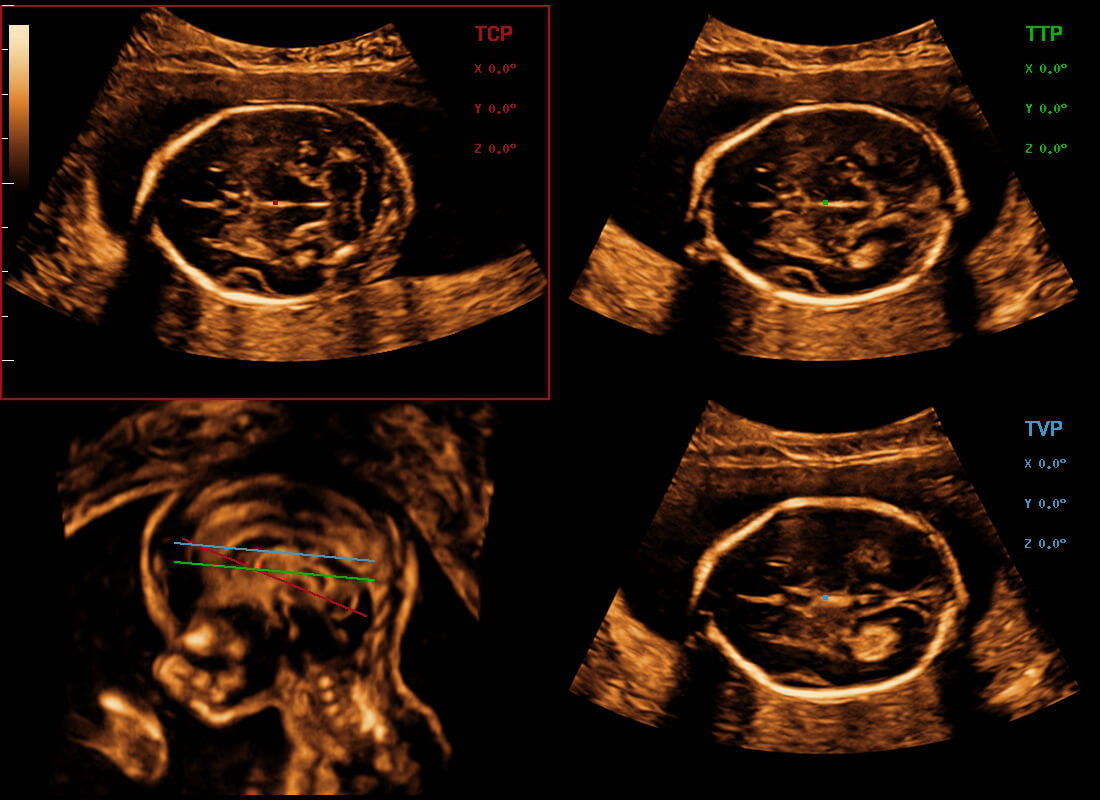

Central nervous system (CNS) malformations are one of the most common congenital abnormalities. Unfortunately, due to imaging limitations such as poor fetal position, acoustic shadowing, and operatorsŌĆÖ poor scanning skills, the MSP is particularly difficult to find in a 2D ultrasound. In this case, a faster and more user-friendly method, which automatically displays the standard planes together with the required measurements in a fetal CNS examination, could significantly boost both the quality and efficiency of clinical diagnoses.?NuewaŌĆÖs intelligent solution of fetal brain can realize automatic acquisition of brain volume data based on intelligent recognition of CNS application scenarios, intelligent generation of four fetal brain standard planes including MSP, automatic measurement of CNS biological items and automatic evaluation of fetal brain volume. More importantly, Nuewa's leading color Doppler technology can provide a clear and sensitive dynamic display of blood flow in the tiny vessels.